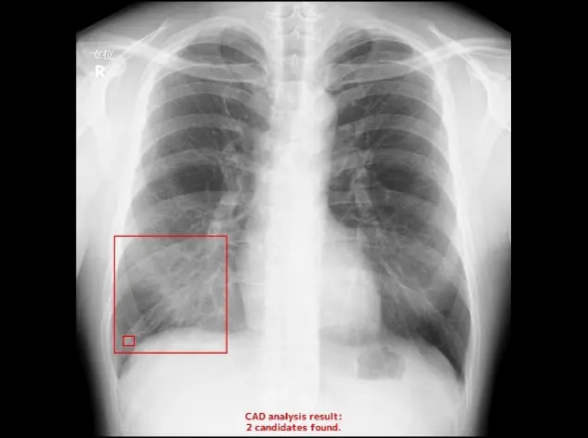

このように異常が検出されると四角のボックスで囲まれます

当院でも昨年11月から胸部のレントゲン診断においてAIによる読影支援(画像解析ソフト)を導入いたしました。

当院が導入した読影支援AIは、医師10名による読影と比較し10%を上回る感度(病気を検出する力)が報告されています。